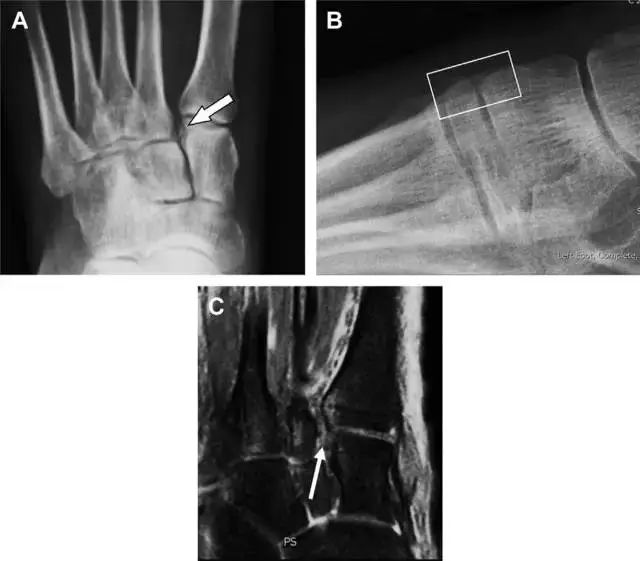

跗跖关节复合体(Lisfranc 关节复合体)损伤

与跗跖关节韧带相关的骨折常由旋前或旋后的跖屈损伤引起。尽管跗跖关节骨折脱位仅占所有骨折的 0.2%,但是约 20% 的这些骨折在初次检查时被漏诊。初次 X 片可能示正常,但是负重位 X 线片常常提示脱位或半脱位。

典型表现:第二跖骨底和内侧楔骨之间的骨折碎片,跖骨间间隙增宽(图 8)。脱位亦可发生在舟骨-内侧楔骨关节,导致另一种变异的跗跖关节损伤(图 9A)。此外,骰骨的小块皮质撕脱在足部斜位片上可清晰显示(图 9B)。

图 8 从马上摔落的患者,跗跖关节骨折。A 正位片示内侧楔骨旁边的小骨折碎片(箭头),第二跖骨底向外半脱位;B 负重位侧位片示第二跖骨相对中间楔骨向背侧轻微移位(长方形);C STIR 序列 MRI 图像示跗跖关节韧带断裂(箭头),第一至第三跖骨、内侧楔骨及中间楔骨均骨髓水肿。

图 9 变异的跗跖关节骨折。A 另一种类型的跗跖关节损伤,中间楔骨向内侧半脱位(弧形箭头),从而使第一、第二跖骨间间隙变宽,需注意,骨折在靠近内侧楔骨处(箭头);B 外侧跗跖关节损伤伴随从骰骨跖骨韧带的骰骨撕脱(箭头),需注意,第五跖骨底近端处存在软组织水肿(空箭头)。